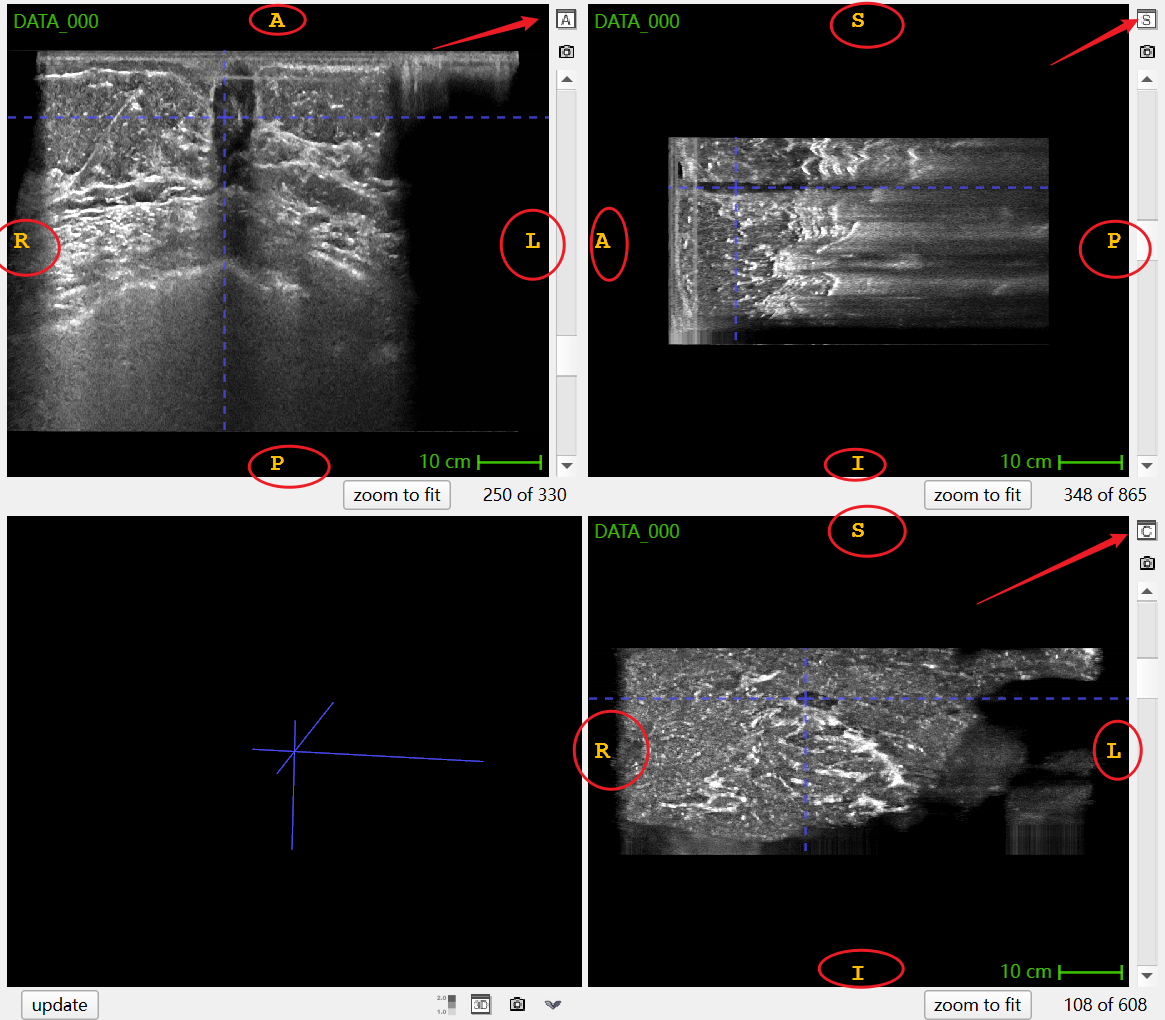

由此我们可以根据医学图像可视化软件ITK-SNAP中的标识识别每个窗口指向的切面

由此我们可以根据医学图像可视化软件ITK-SNAP中的标识识别每个窗口指向的切面